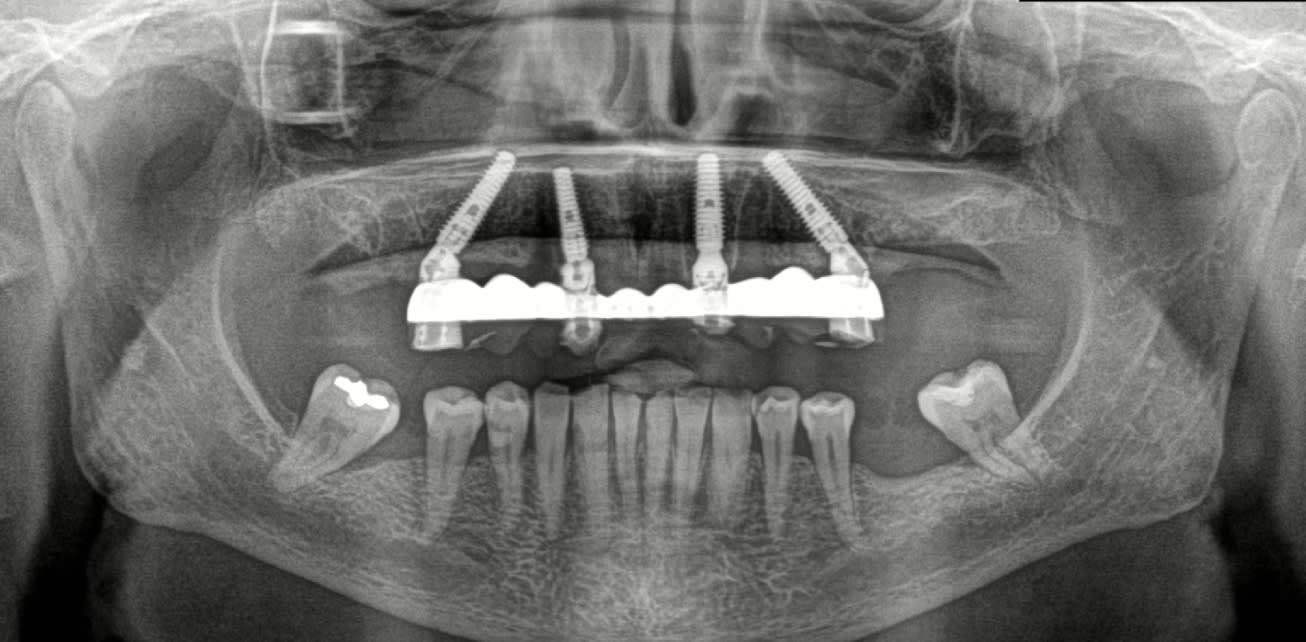

Cas 1 : Implants de 14 et 12 mm, tous en appuis bi-corticale, patiente agé, emergence des implants distaux au niveau des 5. zone assez cicatrisés pour les implants , sauf pour 12 mais qui a un bon ancrage palatin. Pas trop de solution pour en mette 6. rien en distal. Bon cas de AO4 a mon avis.

cas 2 : pareil. un seul implant de 12, 3 en 14 mm. zone edentée tres fine, juste un peu de place la ou j'ai mis l'implant 22. os type 4 en arriere des 7. patiente de 65 ans.

cas 3 : patient 50 ans. avoir des 7 est plus important . implants plus court : 4 de 12, un 14 et un 10. émergence des implant en 14 24 : obligation de chercher un appuis postérieur : deux ptérygoidiens.

Pas de guide à étage : guide appuis osseux, bridge a armature métal avec pilier collé en bouche avec indexation du bridge grâce aux clavettes du guide.